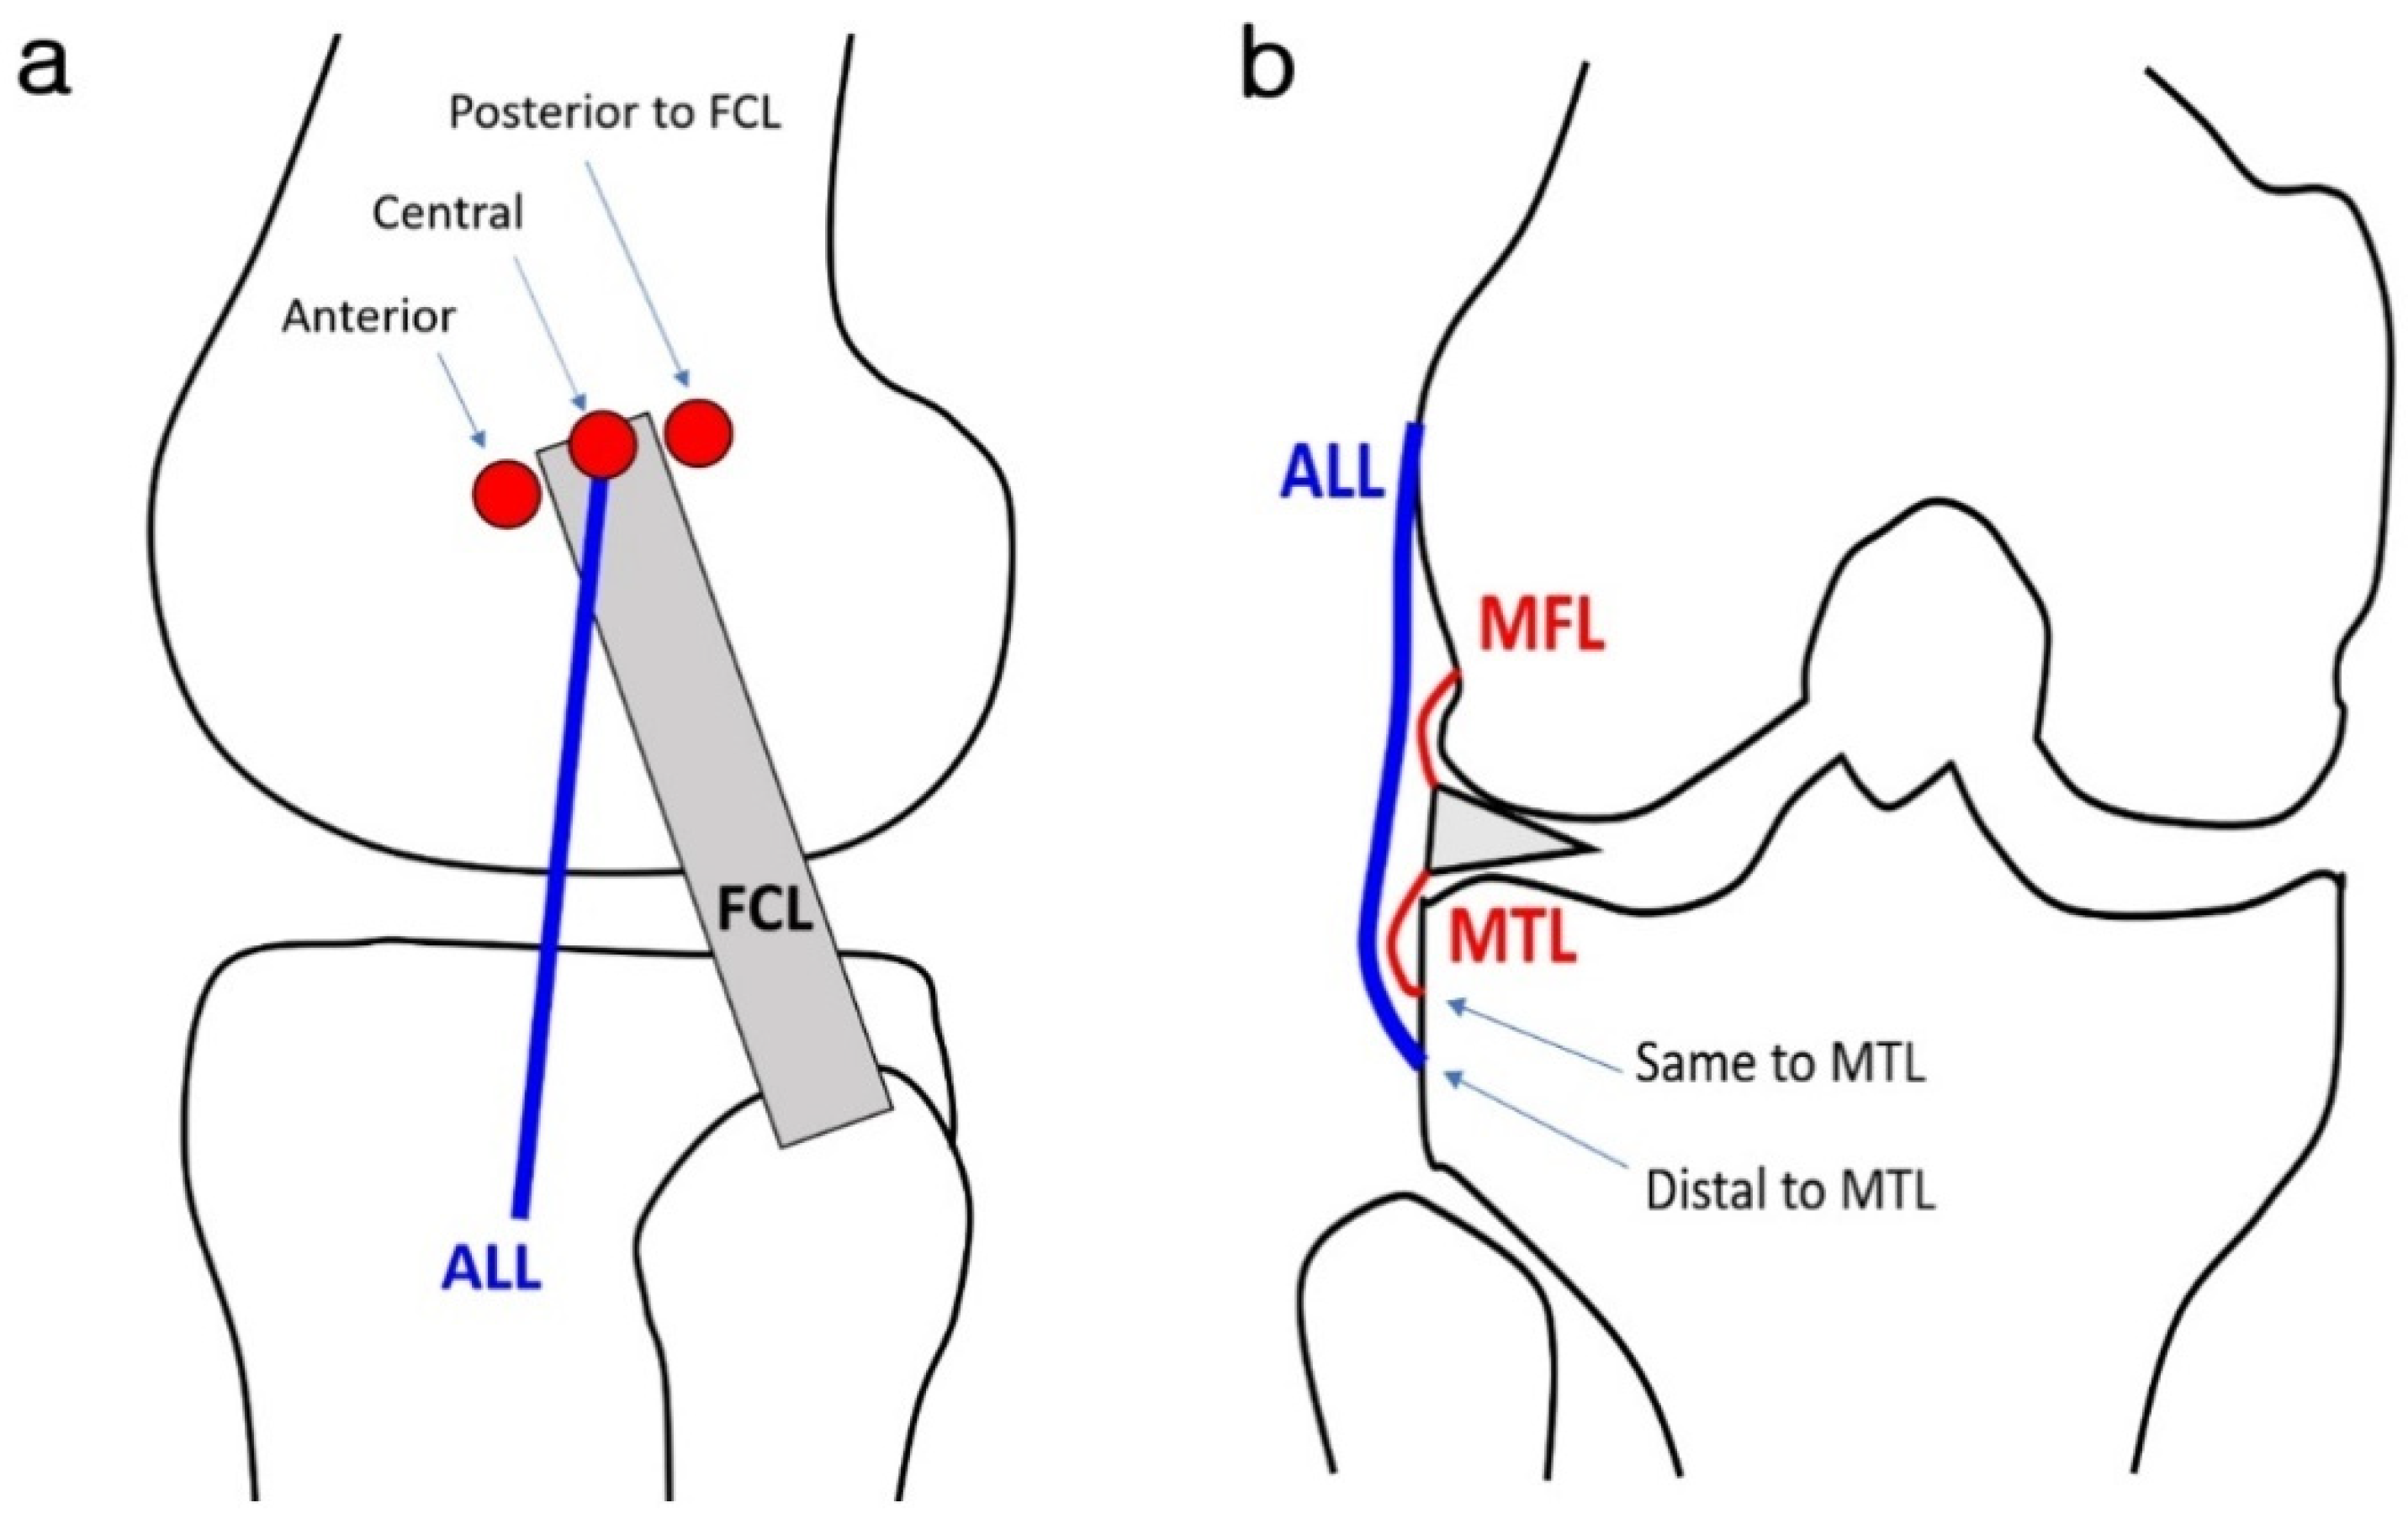

2.3. Image Analysis

3.3. ALL Morphology